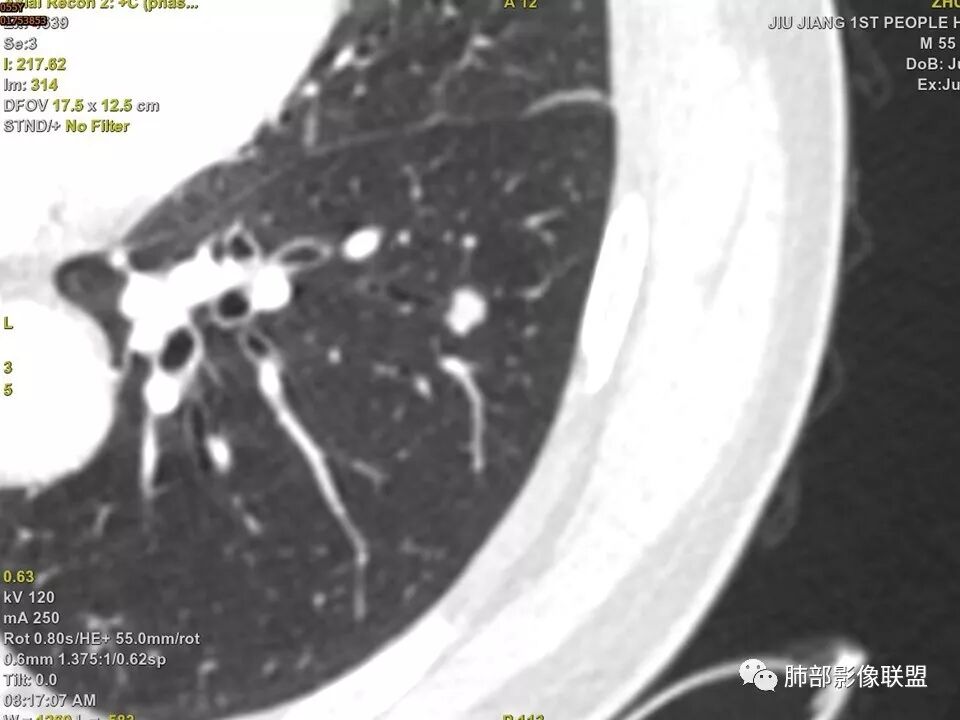

左肺下叶前内基底段结节 深分叶和脐凹 表面部分膨隆 部分收缩 支气管截断 轻度强化 中央有坏死 考虑鳞癌 鉴别炎性结节

中年男性,支气管门口截断、邻近支气管未见管壁增厚,分叶明显,边缘彭隆,内见小坏死灶,周围未见GGO,考虑周围性鳞癌,鉴别炎性肉芽肿。

分叶明显,表面凹凸不平,支气管截断,支持恶性。强化差一些,内有低密度,可疑一下。

左肺下叶前内基底段结节,轮廓凹凸不平,局部边缘平直,密度不均,近段支气管阻塞,增强前后CT值无明显变化,考虑肉芽肿,结核?腺癌代排

左肺下叶前基底段结节,病灶边缘分叶,边缘平直,u型征,可见气管截断,增强可见病灶边缘血管,平扫ct值低,轻度强化。考虑良性病变。

实性结节,以收缩为主,强化弱,支气管截断面呈凹面,浅分叶,肉芽肿性炎

支气管截断,结节轮廓凹凸不平,密度不均,无明显强化,部分边缘呈平直征,考虑结核性肉芽肿,腺癌代排

不是假象,是真的堵了,我工作站薄层做了气管曲面重建,仿真内窥镜也显示堵了

典型CT特征包括:(1)圆形或椭圆形边界清楚的病灶。(2)大小1~4cm,有轻微分叶改变。(3)较均匀的软组织影,多伴有钙化。(4)无毛刺,卫星灶及肺门或纵隔淋巴结肿大。(5)CT增强扫描无强化或轻度强化,其强化可能与软骨瘤间质中的薄壁血管或周围慢性炎症反应有关。